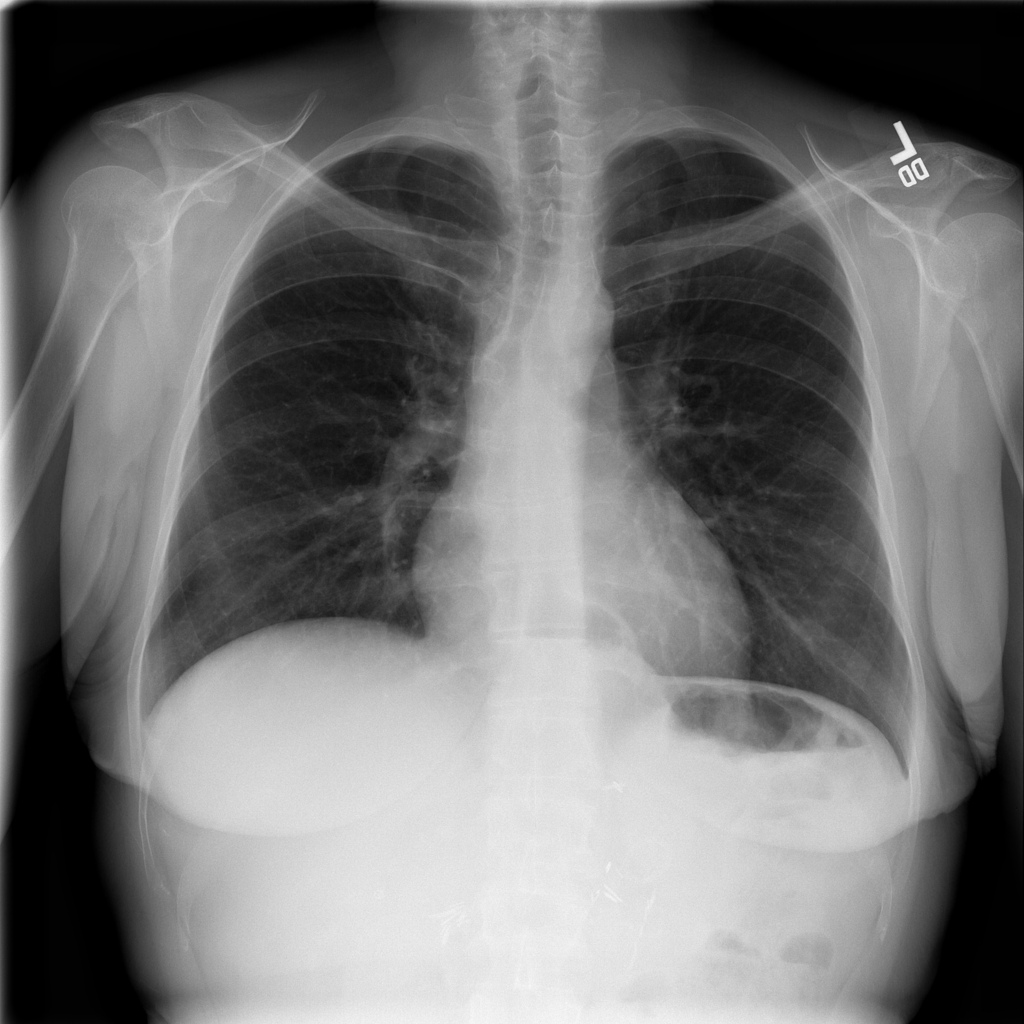

Showing up to 90 reference images for Hernia.

PAT-C048 · IMG-001Hernia

PAT-C048 · IMG-001

PA